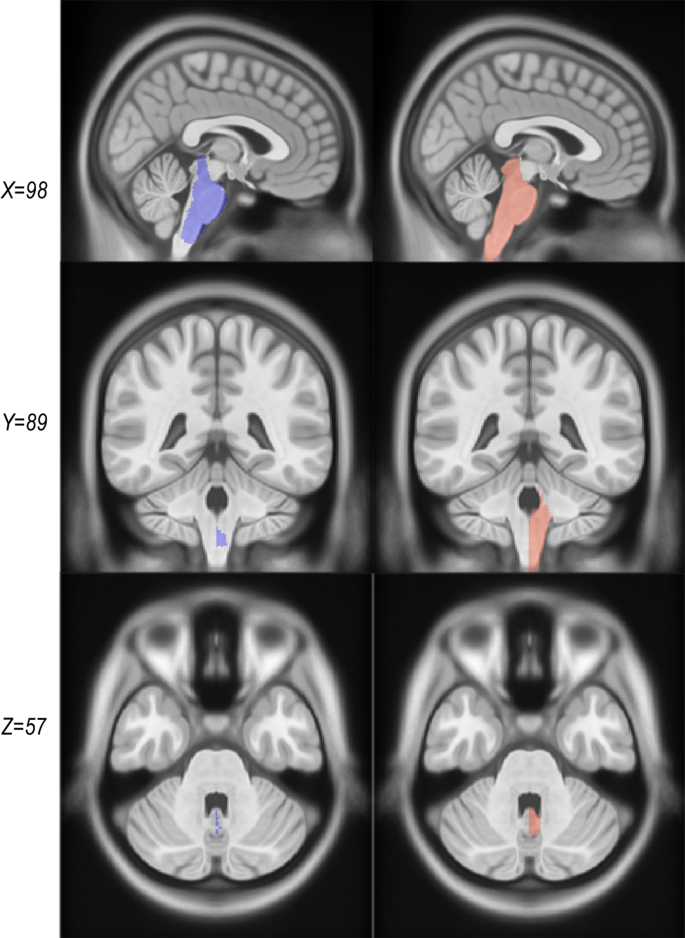

Another significant change in CerebrA from the original warped labels was the brainstem label definition. The brainstem area was manually redefined for the right side and then flipped in the same procedure as all the labels considering the symmetrical feature of the ICBM152 2009c2 template. In addition, boundaries between brainstem and fourth ventricle were carefully defined using the CSF intensity threshold, cerebellar white matter labels within the brainstem area were removed and rostral brainstem delimitation was improved (Fig. 4).